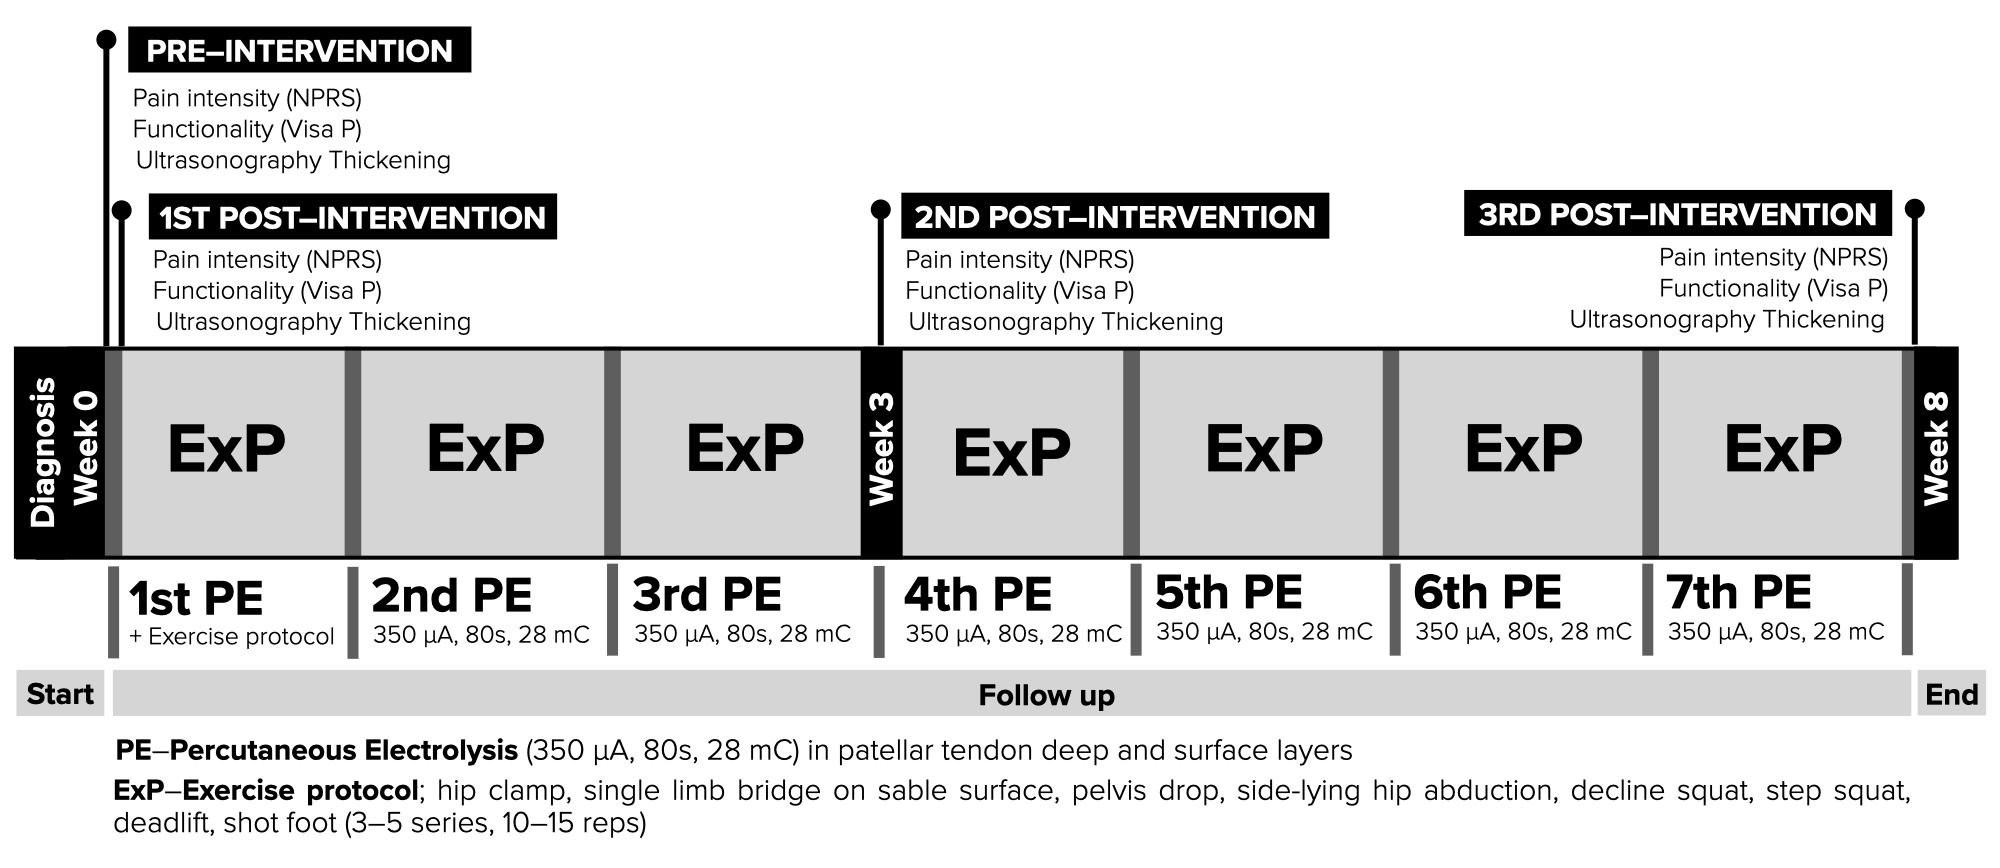

In an 8 weeks period of time, from 4 to 7 sessions of percutaneous electrolysis were performed [9], leaving at least one week between sessions (Table 2).

All patients came to the center to learn the exercises and set the doses of the exercises [33, 34, 35, 36, 37, 38]. They all performed 3 sets of 15 repetitions with a 90 seconds rest between sets of each exercise in those involving a concentric or eccentric phase [13, 15, 18] of hip clams, single limb bridge on stable surface, pelvic drop, sidelying hip abduction, decline squat exercise, step squat, deadlift and short foot (Fig. 4A–H).

Organized care physical therapy information as chronology is presented in Fig. 5.

Fig. 5.

Fig. 5.Diagram of the interventions from the intervention, observation and follow up.